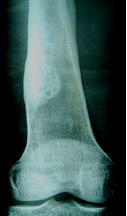

X-ray

Solitary, eccentric lytic lesion

Fibrous Cortical Defect

- < 2 cm

- small cortical lucency

- sharply defined border

Non-Ossifying Fibroma (NOF)

- > 2 cm

- eccentric metaphyseal lesion

- sclerotic margin

- slight expansion of cortex

- usually < 1/3 diameter of bone